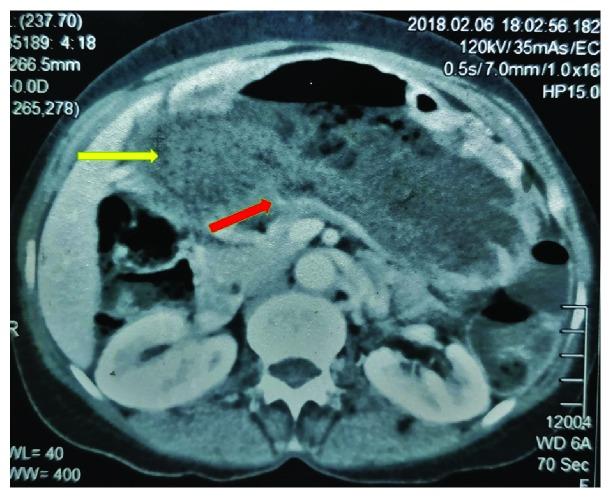

A gastric diverticulum is an outpouching from the stomach wall. It is usually seen in the posterior gastric wall and the gastric antrum. Diverticula arising from the pyloric region are extremely rare. A 59-year-old female presented with progressively worsening symptoms of gastric outlet obstruction associated with dyspepsia and vague abdominal pain for 5 years. A large, thin-walled, wide-mouthed, false gastric diverticulum (filled with undigested food) arising from the pylorus associated with gastric outlet stenosis was found by endoscopy and CT imaging. Multiple biopsies from the region excluded a gastric malignancy. A gastrojejunostomy and jejunojejunostomy were performed to bypass the obstruction which successfully relieved the symptoms. This is an unusual site for gastric diverticula, and when associated with gastric outlet obstruction, further distention of the diverticulum may cause more obstruction with worsening symptoms.

胃憩室是胃壁的一种向外突出。它通常见于胃后壁和胃窦。起源于幽门区的憩室极为罕见。一名59岁女性出现胃出口梗阻症状逐渐加重,伴有消化不良和模糊的腹痛达5年。通过内镜检查和CT成像发现一个起源于幽门并伴有胃出口狭窄的巨大、薄壁、宽口、假性胃憩室(充满未消化食物)。该区域的多次活检排除了胃癌。进行了胃空肠吻合术和空肠空肠吻合术以绕过梗阻,成功缓解了症状。这是胃憩室的一个不寻常部位,当与胃出口梗阻相关时,憩室的进一步扩张可能导致更多梗阻并使症状恶化。